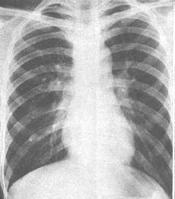

动脉导管原本系胎儿时期肺动脉与主动脉间的正常血流通道。由于该时肺不具呼吸功能,来自右心室的肺动脉血经导管进入降主动脉,而左心室的血液则进入升主动脉,故动脉导管为胚胎时期特殊循环方式所必需。出生后,肺膨胀并承担气体交换功能,肺循环和体循环各司其职,不久导管因废用即自选闭合。如持续不闭合,则构成病态,称为动脉导管未闭(症)。应施行手术,中断其血流。动脉导管未闭并存于肺血流减少的紫绀型心脏病时,导管是其赖以存活的重要条件,当作别论。动脉导管未闭是一种较常见的先天性心血管畸形,占先天性心脏病总数的12~15%。女性约两倍于男性。约10%的病例并存其他心血管畸形。